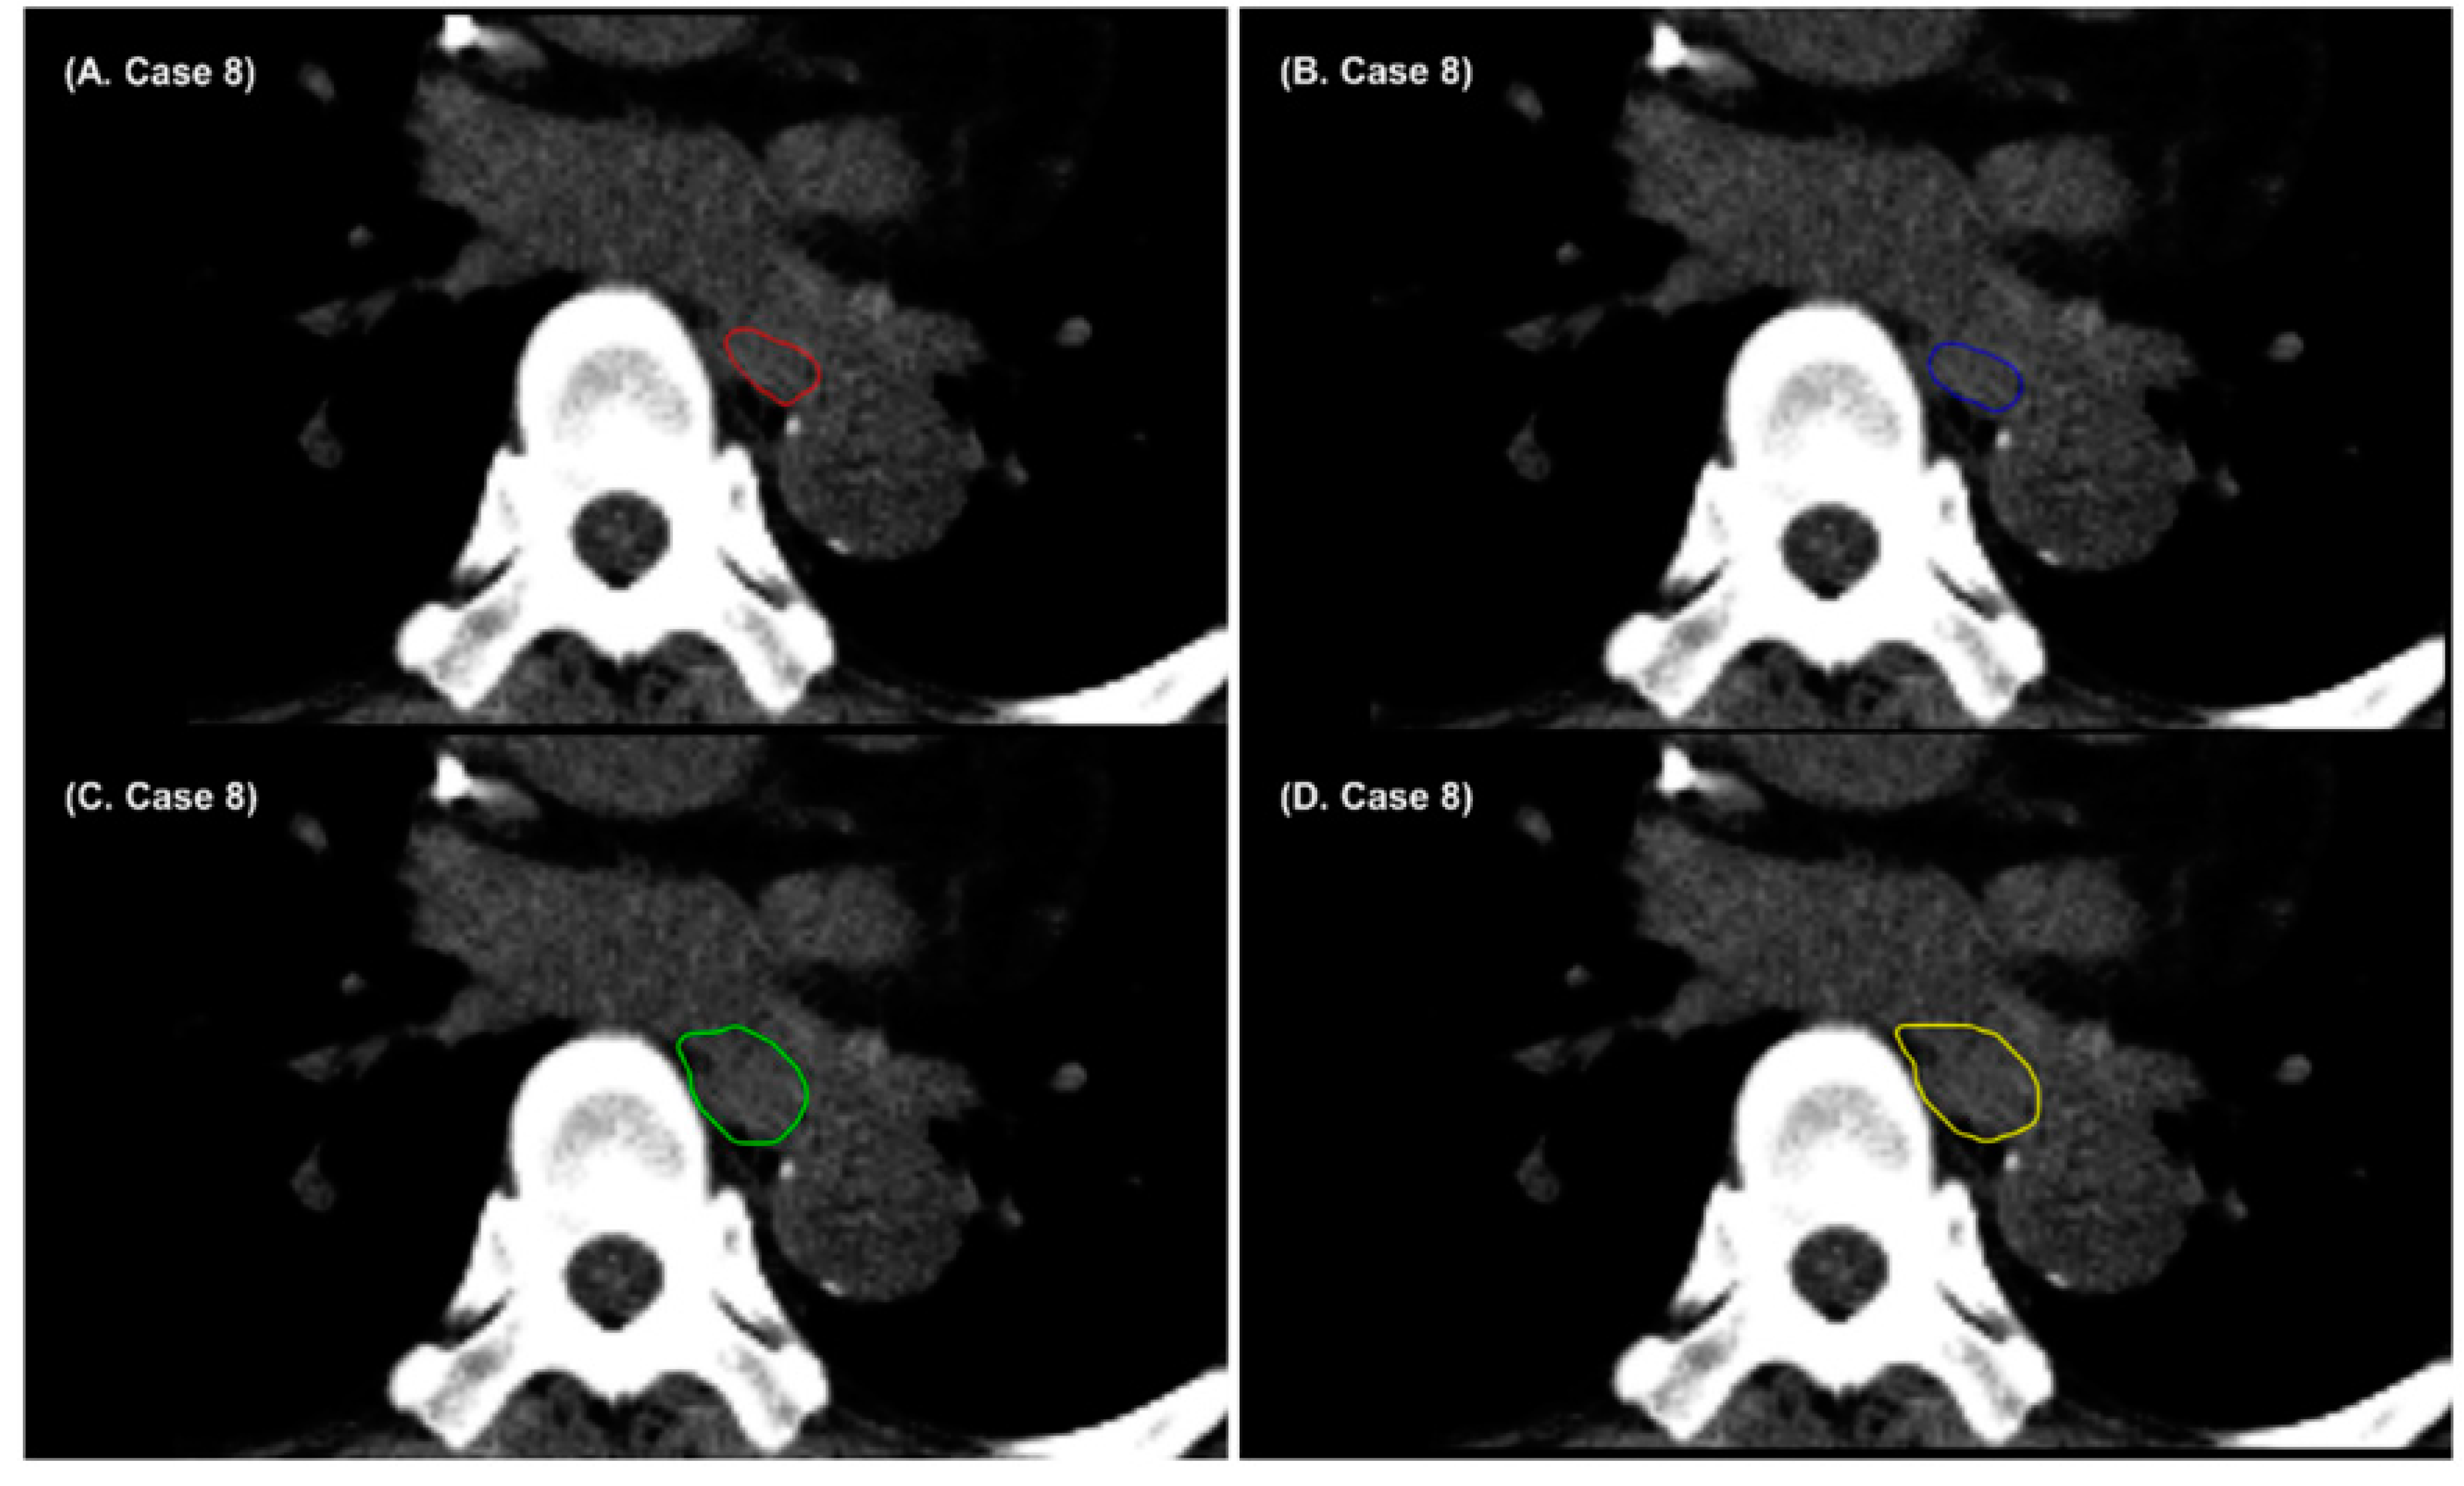

- Chung, S.Y.; Chang, J.S.; Choi, M.S.; Chang, Y.; Choi, B.S.; Chun, J.; Keum, K.C.; Kim, J.S.; Kim, Y.B. Clinical feasibility of deep learning-based auto-segmentation of target volumes and organs-at-risk in breast cancer patients after breast-conserving surgery. Radiat. Oncol. 2021, 16, 1–10. [Google Scholar] [CrossRef] [PubMed]

- Choi, M.S.; Choi, B.S.; Chung, S.Y.; Kim, N.; Chun, J.; Kim, Y.B.; Chang, J.S.; Kim, J.S. Clinical evaluation of atlas-and deep learning-based automatic segmentation of multiple organs and clinical target volumes for breast cancer. Radiother. Oncol. 2020, 153, 139–145. [Google Scholar] [CrossRef]